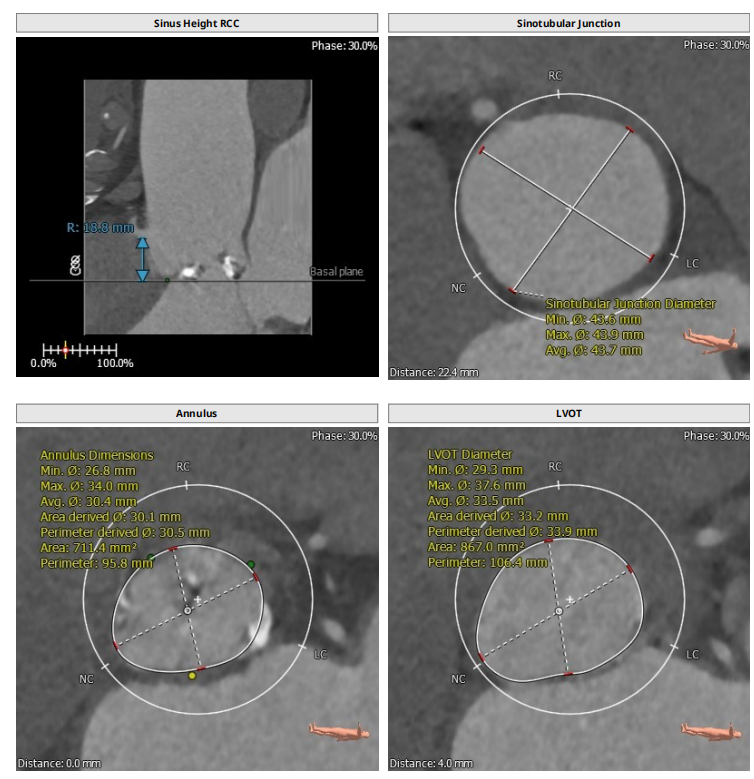

此例病人Type1二叶瓣,左右冠瓣融合,右无疑似融合,重度钙化,瓣环30.5,LVOT33.9,左右冠高度为16.9mm与18.8mm,右无融合离对侧28-30左右,STJ43.7,升主47.9,整体结构极大,心脏角度65度,近乎横位。